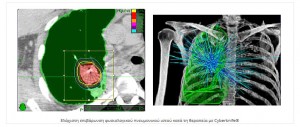

Η ακτινοχειρουργική με CyberKnife αντιπροσωπεύει μία πανίσχυρη και μεγάλης ακρίβειας τεχνική για ασθενείς με αρχική, υποτροπή ή μεταστατική εντόπιση όγκου στον πνεύμονα. Η θεραπεία είναι ασφαλής να δοθεί σε ασθενείς που δεν μπορούν λόγω άλλων παθολογικών καταστάσεων να χειρουργηθούν και  προσφέρει μία πολύ καλή θεραπευτική επιλογή σε ασθενείς με υποτροπιάζουσα ή εμμένουσα νόσο που πριν είχαν ελάχιστες αν όχι καμία, δραστική θεραπεία ικανή να τους βοηθήσει.